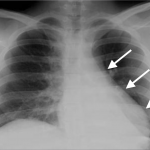

Some key features to keep in mind for the appearance of atelectasis on a chest X-ray are:

- Presence of opacity: fundamentally the collapse of this lung parenchyma will appear as an opacity over a portion of the lung field. On a chest X-ray this will show up as “increased white”.

- Sharp margins: generally the portions of collapsed lung tissue will have sharp margins that can be appreciated radiographically on an X-ray.

- Mediastinal shift toward the opacification: in certain cases the lung collapse will cause the shift of mediastinal structures toward the atelectasis (due to “vacuum” generated by the collapse of this lung tissue). This will be more obvious in larger collapses (such as complete atelectasis).

RIGHT LOWER LOBE ATELECTASIS

The archive below organizes different examples of a right lower lobe atelectasis. It will really be the anatomical location of the finding that will help diagnosis this SPECIFIC subtype of atelectasis.Whats more, this type of atelectasis often obscures the border of the right diaphragm. Click on the thumbnails below to view the archive.